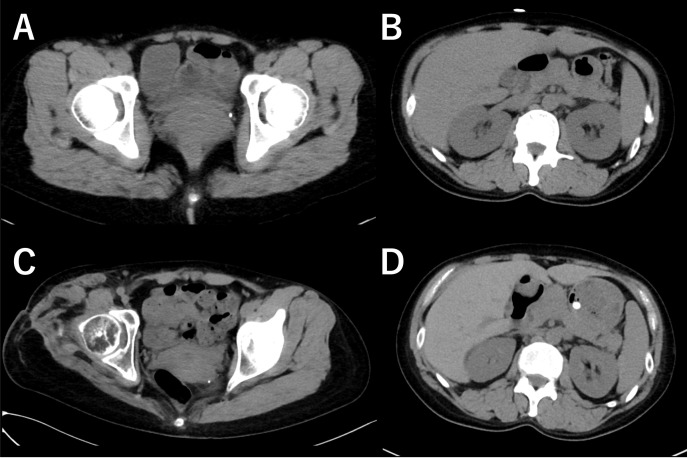

Case: A 39-year-old woman developed STSS. She underwent 18 surgeries and vacuum-assisted closure therapy, which resulted in ultra-short right transfemoral amputation. With a strong desire to walk again, she began fitting for a provisional prosthesis 3 months post-amputation. Given the preserved hip muscle strength, an ultra-short transfemoral prosthesis was selected over a hip disarticulation prosthesis. The key components included a plug-in quadrilateral socket, a belt used to suspend the transfemoral prosthesis, a hydraulic knee joint, and an energy-storing foot. She regained walking ability using crutches. To address pain and skin issues in the stump load-bearing area, compression and adhesion were improved using thick fabric spats. Muscle mass, including that of the paraspinal muscles, was maintained during follow-up evaluations using computed tomography, dual-energy X-ray absorptiometry, and bioelectrical impedance analysis. The phantom limb pain in the right leg diminished with medication and prosthetic training. Her quality-of-life scores measured using the 36-item Short Form Questionnaire and the Prosthesis Evaluation Questionnaire also showed improvement. She was discharged home 5 months post-amputation.